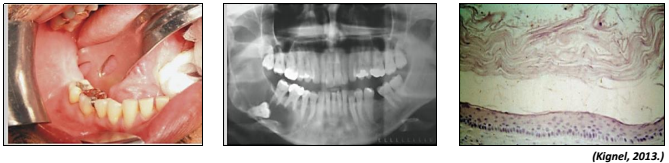

Observe as imagens a seguir referentes à mesma lesão.

enunciado 620003-1

Trata-se de um cisto com critérios histológicos bem definidos, com alta taxa de recidiva. Origina-se a partir de remanescentes da lâmina dentária. Geralmente possui comportamento benigno, porém agressivo. Apresenta-se em qualquer idade, com maior incidência entre a 2 e 3 décadas de vida, raramente abaixo dos 10 anos de idade. A mandíbula é invariavelmente mais afetada que a maxila. Sua tendência de crescimento é ocupar os espaços medulares gerando pouca expansão óssea. As informações se referem ao cisto: